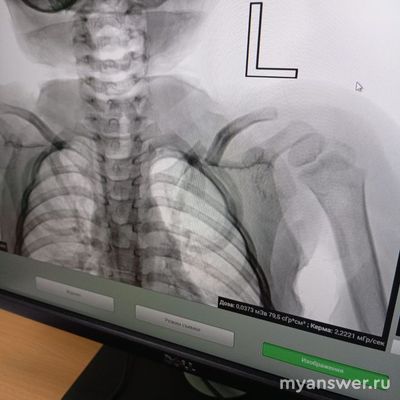

По своему многолетнему хирургическому опыты, могу сказать, отломки ключицы, даже не сопоставленные в основном не плохо срастаются и довольно быстро. Да, будет косметическая деформация, в области ключицы за счёт заметной костной мозоли, когда отломки срастаются не конец в конец, а бок в бок. Серьёзных нарушений функции плечевого сустава ожидать не приходится. В отношении выбора хирургического лечения неправильного стояния костных отломков значение будет иметь возраст пациента. В молодом возрасте, металлоостеосинтез перелома ключицы со смещением, имеет значение, а для пенсионера, сойдёт и так, как есть. Достаточно трёх недель походить с "кольцами", или повязкой "Дезо" из эластического бинта, это чтобы меньше болело. А дальше повреждение верхнего плечевого пояса само захочет работать. А для конкретики ответа, нужно видеть рентген снимок, на котором указывается и возраст больного.

Добрый день! Ребёнку один год и 11 месяцев

Насколько опасен невправленный перелом ключицы со смещением?